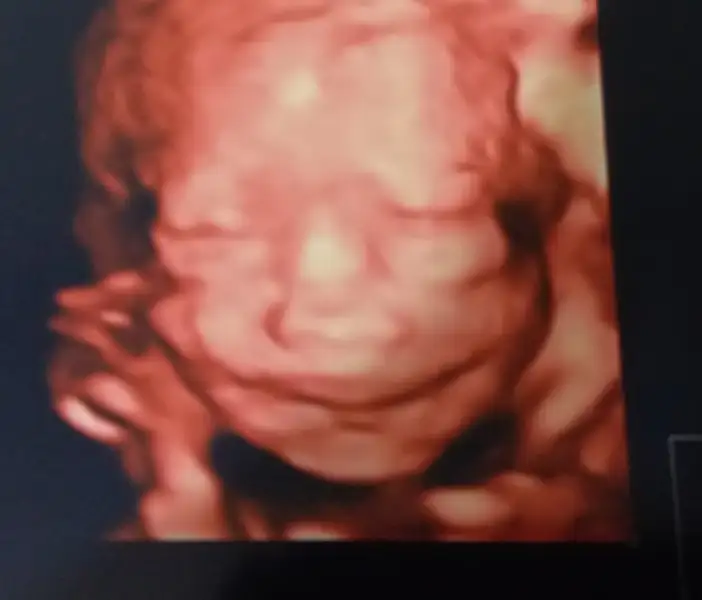

Selamlar hanımlar. Ayrıntılı ultrasondan çıktım. Çok şükür herşey yolunda. Enteresan bir durusu vardı doktor çok karakteristik bir özelliği var dedi. Eşime baktı babasına benziyor yakışıklı olacak ama babasını geçecek dedi. Ama sıpa o kadar kısacık gosterdiki yüzünü anlık görebildik. Uyuyordu çok uykucu olacak dedi ama bir uyandı bir uyandı kıpır kıpır.

Enes beyin yuzunude goremedik video ve fotoğraf verdiler.Evimize dönüyoruz